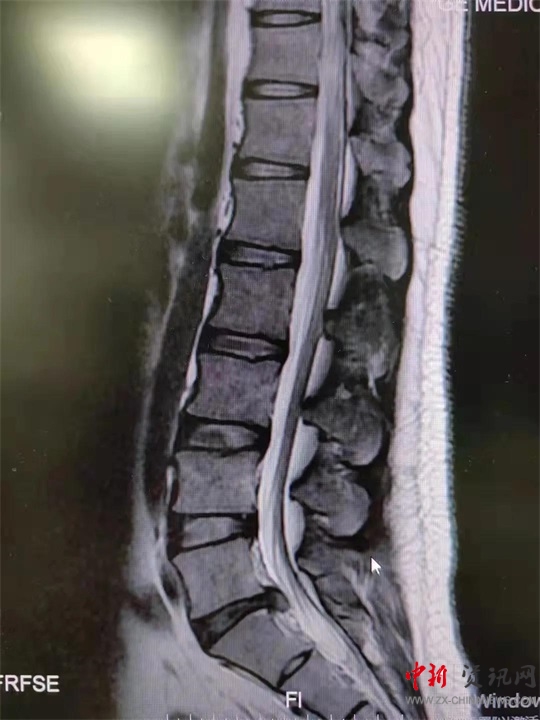

9月初,盧先生來(lái)到駐馬店市第一人民醫(yī)院就診。影像學(xué)檢查提示腰5骶1椎間盤(pán)突出;颊甙Y狀、體征與影像學(xué)表現(xiàn)相符,腰椎間盤(pán)突出癥診斷明確。結(jié)合患者情況,蔣學(xué)國(guó)主任團(tuán)隊(duì)決定舍棄傳統(tǒng)手術(shù)方案,為患者實(shí)施UBE技術(shù)下腰椎間盤(pán)髓核摘除術(shù),這也是UBE技術(shù)在西院區(qū)的首次應(yīng)用。